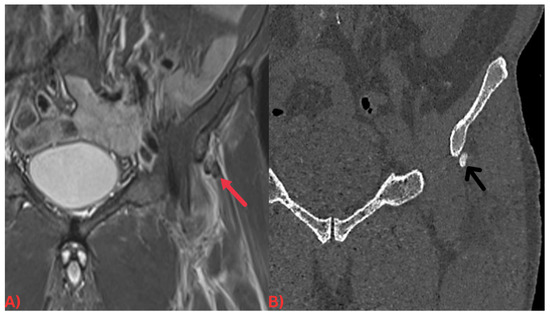

Computed tomography (CT) offers an in-depth visualization of hydroxyapatite deposits, elucidating their size, shape, and location. CT scans reveal these deposits as high-density zones within soft tissues, often associated with the inflammation around them, apparent as increased attenuation in adjacent soft tissues [23] (Figure 2). The high-density portrayal of hydroxyapatite deposits on CT scans stems from hydroxyapatite’s high calcium content, which absorbs more X-rays than the surrounding soft tissues [23]. The detailed information offered by CT scans can shape treatment strategies for HADD patients, such as by guiding surgical interventions [25]. The hydroxyapatite deposits’ association with surrounding inflammation can be gauged on a CT as decreased attenuation in adjacent soft tissues from the soft tissue edema. This observation can confirm the diagnosis of HADD and evaluate the disease’s extent [25].

Figure 2. (A) Coronal short tau inversion recovery (STIR) MRI of the pelvis demonstrating an ill-defined low signal intensity focus at the origin of the left rectus femoris tendon (red arrow) with surrounding soft tissue edema. (B) Coronal CT image of the pelvis. Note how the calcification is more easily discernable on the CT image (black arrow).